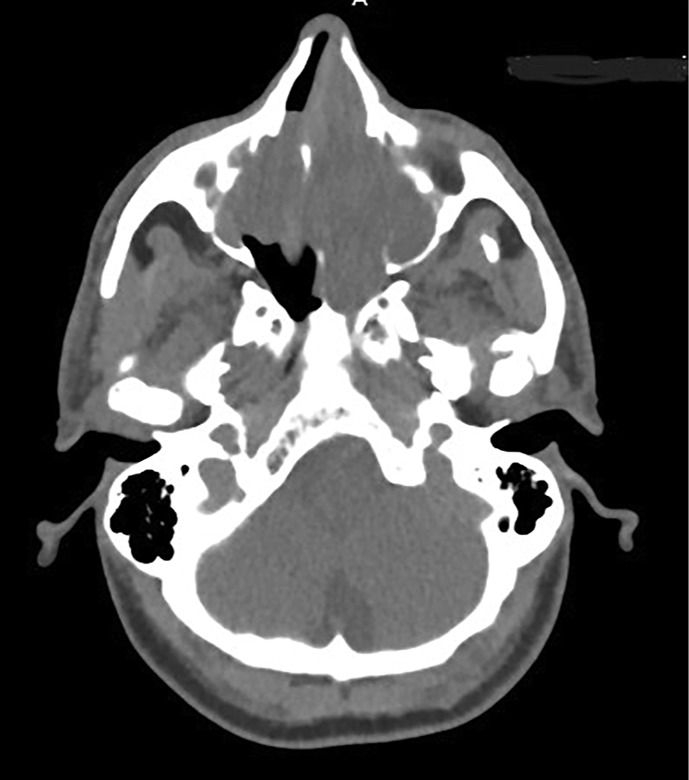

Case presentation: A 67-year-old male reported 10 months of nasal obstruction, mouth breathing, and sleep disturbances. The initial evaluation for foreign body obstruction revealed septal deviation and low-density sinonasal tissue on CT. MRI identified a 7 × 4.5 × 7 cm heterogeneous lesion invading nasal structures, paranasal sinuses, and nasopharynx with diffusion restriction. Tru-cut biopsy confirmed ACC via cribriform, tubular, and solid basaloid cell patterns, pseudocystic spaces, biphasic ductal-myoepithelial cells, and perineural invasion. Immunohistochemistry (CK7, CD117, p63, S100) supported the diagnosis, with tumor-free margins and no metastases. Multimodal therapy (30 VMAT sessions, 4 cisplatin-vinorelbine cycles) improved symptoms.

Abstract Image